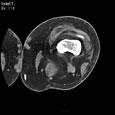

Синовиальная киста подколенной ямки. Синовиальная киста подколенной ямки OpenWindow.document.write("Medicus Amicus - Медицинские изображения")

Пациент R., 59 лет

Синовиальная киста подколенной ямки.

ЦКБ5 Южной железной дороги, отделение лучевой диагностики.

Протокол.

Контрастированы поверхностные и глубокие вены левого коленного сустава. Костно-деструктивные изменения не определяются. Дегенеративно-дистрофические изменения в проксимальном бежберцовом сочленении. В области подколенной ямки, прилежа медиально и кзади к подколенной мышце, полостное образование размерами 42х36х56 мм, содержащее жидкость (16-20 HU) с четкими ровными контурами, без признаков сдавления глубоких вен подколенной ямки.